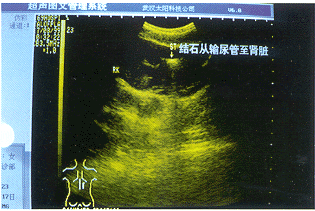

患者女,11岁,因右侧腰部轻度胀痛2年就诊,行泌尿系超声检查,先探查膀胱区时见右侧输尿管下段重度扩张(图1),内径23mm,其内见约6mm×5mm强回声,伴声影。在测量结石大小时,见输尿管有节律地明显收缩扩张运动,结石则似“金鱼吞食”逆其上行,约2分钟后结石到达肾中部(图2),B超诊断:1、动态右输尿管(或肾)结石;2、右输尿管重度扩张。

图2 右肾结石

患者经手术证实为右输尿管膀胱开口处粘连闭锁,导致输尿管重度扩张,并非结石所致,B超探查时其明显收缩运动可能与探头挤压刺激有关。故在检查泌尿系时有必要进行全程探查,以免漏诊。